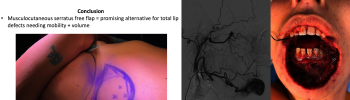

Functional Total Lip Reconstruction with Free Neurotized Musculocutaneous Serratus Flap: A Case report